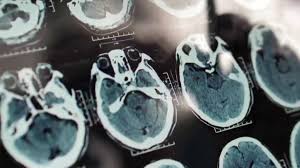

Nguy cơ khởi phát chứng sa sút trí tuệ (dementia) có thể cao hơn nhiều so với trước đây, theo một nghiên cứu được công bố hôm thứ Hai trên tạp chí Nature Medicine.

Theo Trung tâm Kiểm soát và Phòng ngừa Dịch bệnh (CDC), khoảng 10% người Mỹ trên 65 tuổi đã được chẩn đoán mắc chứng sa sút trí tuệ. Gần 7 triệu người tại Mỹ mắc bệnh Alzheimer, dạng phổ biến nhất của chứng sa sút trí tuệ.

Theo nghiên cứu, nguy cơ trung bình mắc chứng sa sút trí tuệ trong suốt cuộc đời của một người 55 tuổi là 42%, nhưng nguy cơ không giống nhau ở mọi độ tuổi. Nguy cơ này tăng cao đáng kể sau sinh nhật lần thứ 85. Từ 55 đến 75 tuổi, nguy cơ phát triển chứng sa sút trí tuệ của một người trung bình là 4%. Khi bước sang tuổi 85, nguy cơ tăng lên khoảng 20%. Nguy cơ cao đến 42% cho đến khi một người 95 tuổi.